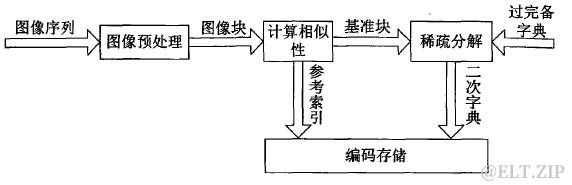

压缩流程如下:

图四.基于稀疏表示的序列图像压缩流程